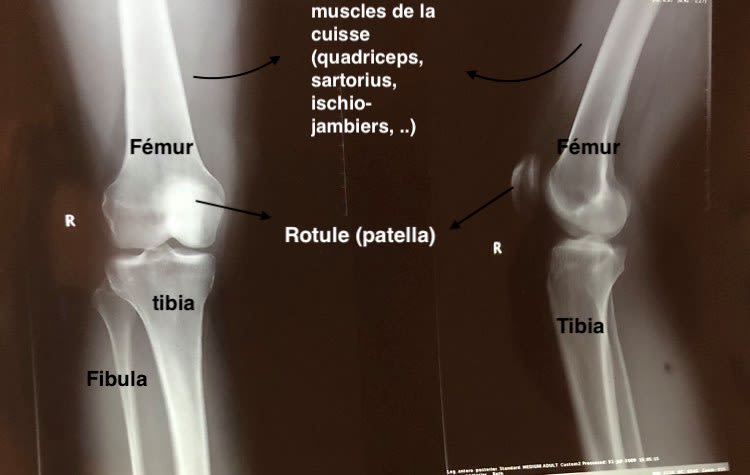

Si dessous, une radiologie personnelle d'un genou. pour vous aider à mieux vous y retrouver j'ai indiqué les différents os visibles.